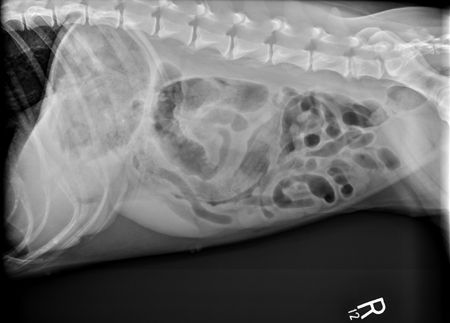

Also, things are hidden on the down side that you can't usually see until you flip the patient over to allow gas in the region to provide radiographic contrast with the soft tissue and fluid that may be present, especially in the abdomen. For example, in most dogs linear foreign bodies get caught in the pylorus of the stomach. A right lateral radiograph puts that side down so it's surrounded by fluid. Therefore the soft tissue of the foreign body blends with the fluid in the stomach and you can't see the lesion. If you're worried about a linear foreign body, take a left lateral radiograph to put gas in the pylorus, allowing you to see the foreign body (Figure 1).

Figure 1A: This left lateral radiograph shows a foreign body (sock) within the pylorus of the stomach and the descending duodenum. Note that you can barely see the linear striations of the lesion on the right lateral radiograph (Figure 1B), but it is clearly seen on the left lateral when gas is present in the fundus. (Radiography images courtesy of Dr. Anthony Pease.)

Figure 1B: Right lateral view.